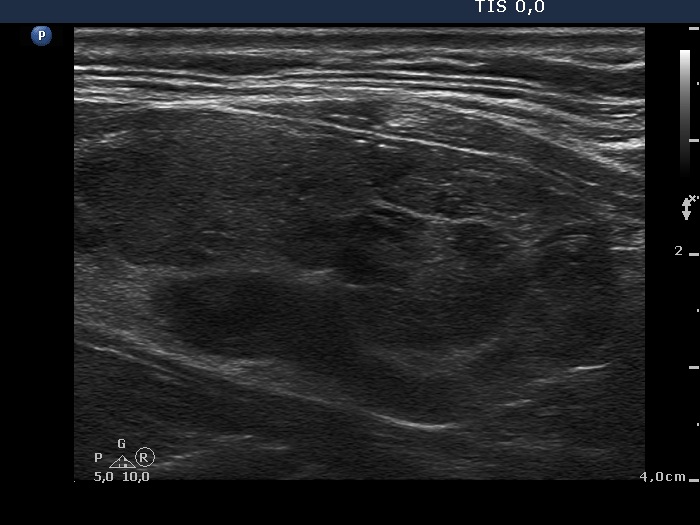

|

Papillary carcinoma (histological diagnosis) - case conp 035 |

The thyroid presented in the left images is composed of moderately hypoechogenic and hypoechogenic nodules, while the lobe in the malignant case is diffusely hypoechogenic and has a less hypoechogenic but more inhomogeneous lesion in its dorsal part. Both the left thyroid and the malignant nodule in the right images have hyperechogenic granules and lines which correspond to a connective tissue.